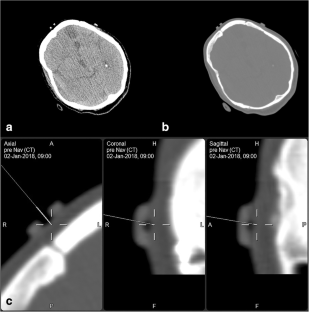

Fig. 1